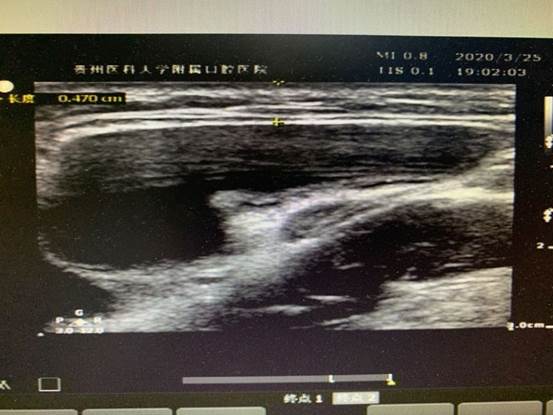

疫情以来,心电图室及超声室每一位医护人员都认真学习疫情防控方案、要求,遵循医院的安排,心电图室根据患者需求科学排班,24小时随时待命。多次夜间急诊、周末节假日出诊,心电图室积极配合,第一时间为患者行床旁心电图,及时解决一线的燃眉之急;超声室共接诊病人36人次,其中多以颌面部包块病人为主,并积极配合口外医生实施手术及穿刺,在与临床医生配合下,确诊了两例舌下腺囊肿(口外型)病人,一例已手术。